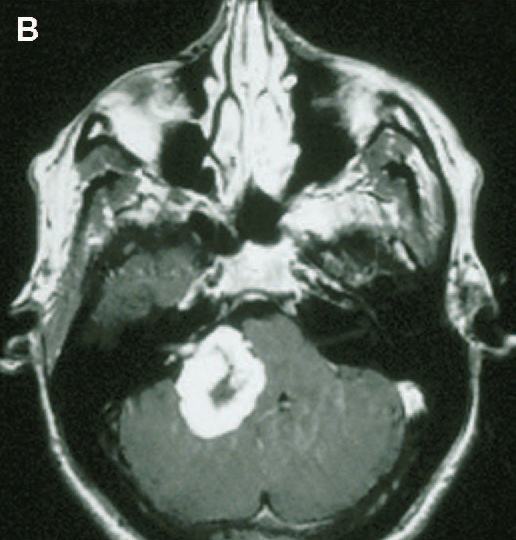

Case 5

该患者肿瘤体积较大,术后听力保留。A. 术前MRI和电测听结果,语言辨别值为96%。B. 术后MRI和电测听结果,语言辨别值为100%。